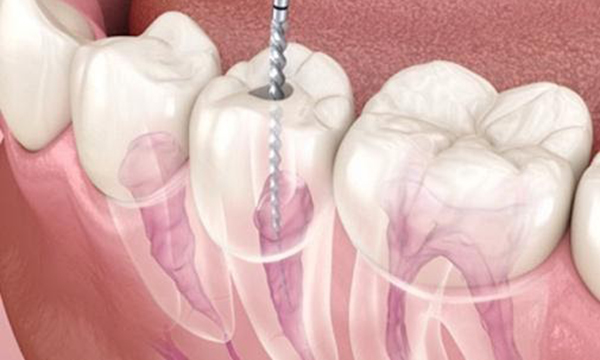

根管治療の具体的な治療内容

歯の根っこ(神経)の中から痛みや腫れの原因である「感染した汚染物」を、取り除く治療です。

針のような道具を使って、感染した汚染物をとりのぞいていきます。

汚れを取り除いた箇所をキレイに清掃・消毒して、お薬で埋めるまでが根管治療です。

抜髄の流れ

1. 麻酔をする

2. 神経の入口まで歯を削る

3. 針のような道具を使って、歯の神経を

取り除く

4. 神経をとった空洞を清掃、消毒する

5. キレイになるまで繰り返す

(数回かかることがあります)

6. キレイになった神経の空洞に最終的なクスリを詰める

7. レントゲン写真で状態を確認する

その後、歯そのものの修復をおこなっていきます。